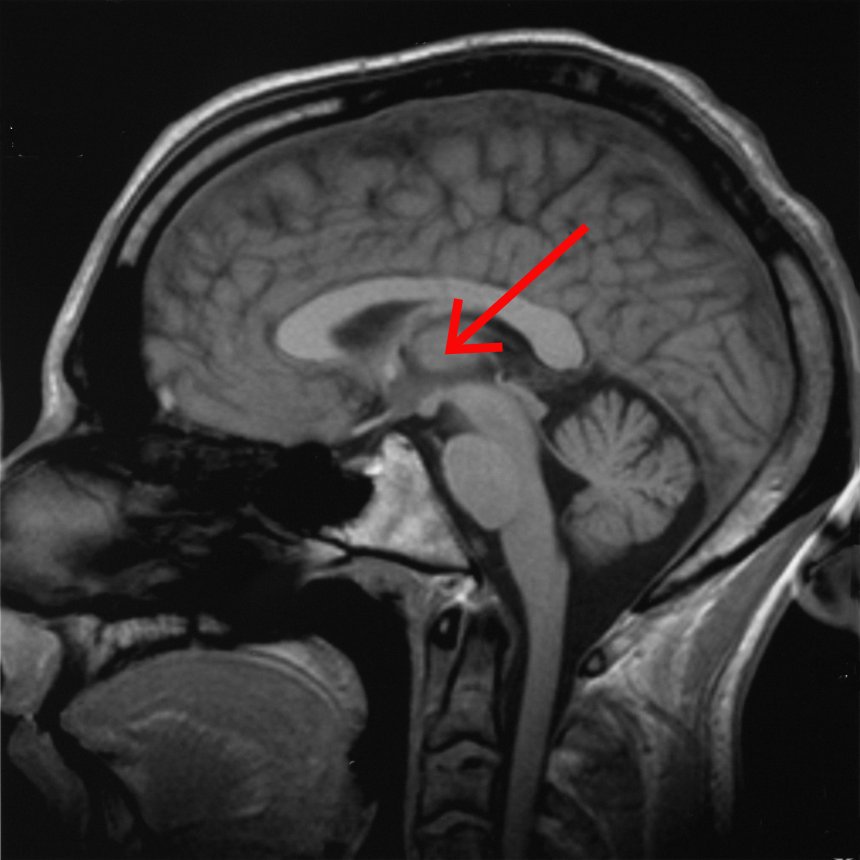

The thalamus is a small, bilateral structure centrally located in the brain. It is highly connected to various brain areas including the hypothalamus, basal ganglia, hippocampus, and more. The thalamus is involved in the regulation of attention, motor coordination, working memory and sleep-wake cycles. In addition, the thalamus regulates sensory information.

The thalamus receives and processes all sensory information except olfactory information. This includes visual, auditory, somatosensory and gustatory information. Essentially, it acts as a gatekeeper, filtering and directing sensory information to the corresponding areas of the cerebral cortex for further interpretation and awareness.

image.thalamus

Original by Albert Kok Credits:Wikipedia. CC_BY_3.0